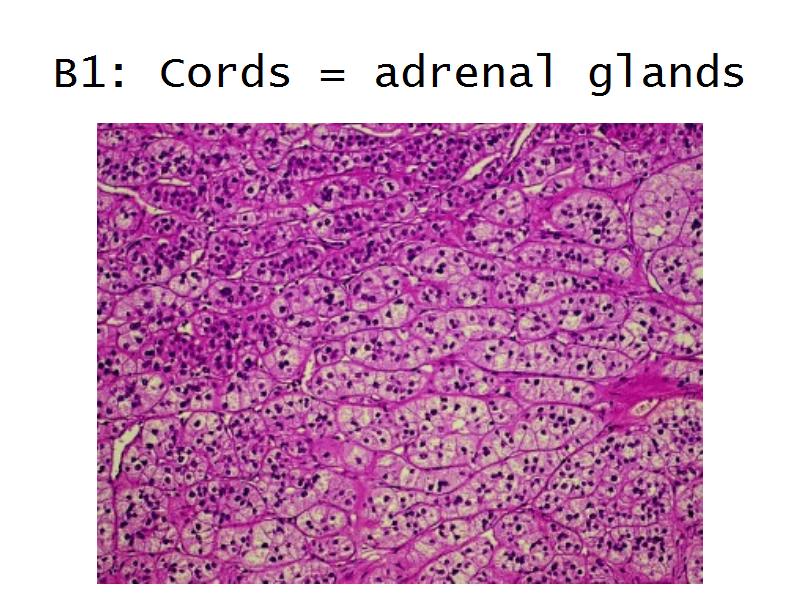

Question B1 to B4

For each of the following 4 slides

Which gland is arranged as:

Adrenal glands

Capsule

Cortex - how many zones?

Medulla

Hormones of each?